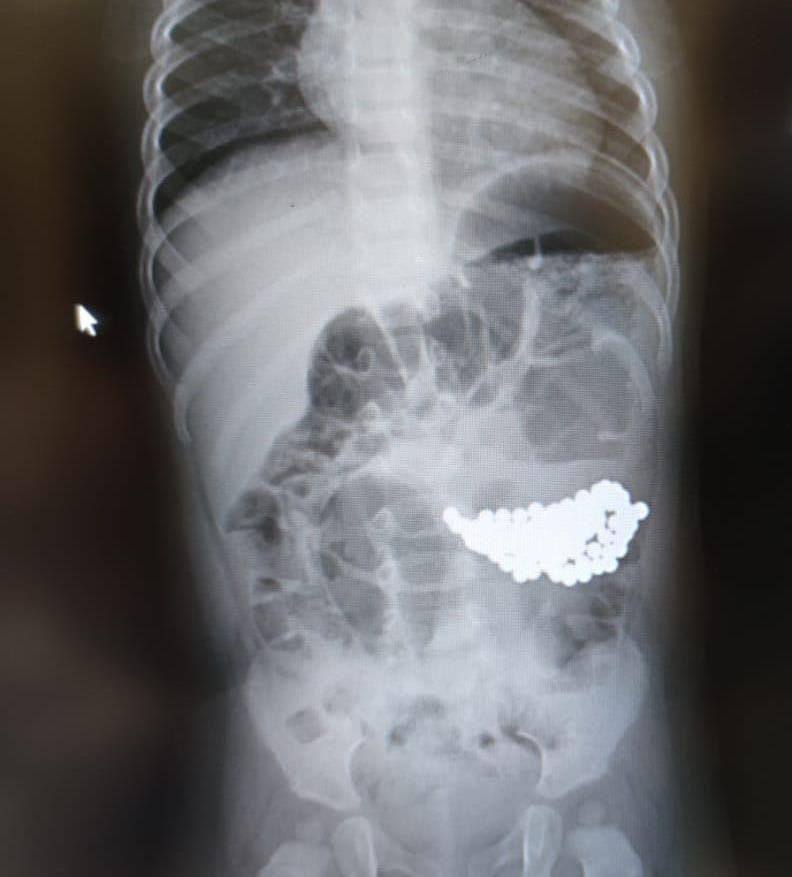

Хирурги детской больницы №9 им. Сперанского достали из желудка годовалого ребенка 117 магнитных шариков.

Мальчик играл с магнитным конструктором старшей сестры. Когда мама собирала игрушки, тогда и обнаружила, что не хватает половины набора магнитного конструктора. К счастью, родители вовремя вызвали скорую. С ребёнком все хорошо, готовится к выписке.